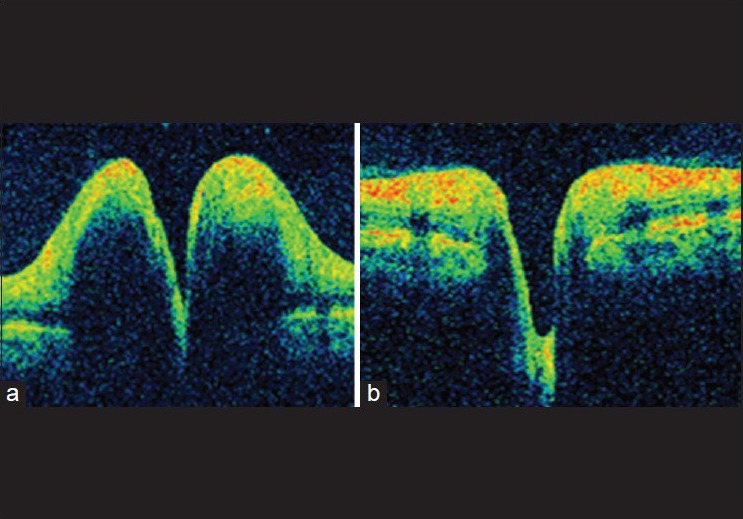

All 30 patients with TP had OCT taken during the acute phase of raised ICP. All patients with papilledema had a resolution of disc edema after the treatment. The RNFL thickness decreased after the commencement of treatment [Fig. 3].

Figure 3.

Pre- (a) and post-treatment (b) retinal nerve fiber layer in papilledema

Use of optical coherence tomography in monitoring papilledema

In pediatric patients with papilledema, an objective method of evaluation of disc swelling while monitoring the treatment is an easy option. El-Dairi et al. have shown the feasibility and accuracy of the same in pediatric age group.[12] Rebolleda and Muñoz-Negrete have quantitatively correlated RNFL thickness with visual field sensitivity losses.[13] They showed that for every 10 μm of mean RNFL thickness increase at baseline, there was a 0.6-dB decrease in mean deviation at the last follow-up. The main problem using OCT to observe patients with papilledema, is there is no way, based on OCT alone, to determine, when RNFL thickness returns toward normal, whether it implies patients are improving or that they are actually losing nerve fibers. A discrepancy between OCT and visual field testing can be helpful. Hence, serial OCT imaging and perimetry can be the standard in monitoring papilledema. Since all our patients showed a decrease in papilledema after initiation of treatment, the serial OCT showed a decrease in the RNFL thickness in all the patients [Fig. 3]. We also noticed discrete hyper reflective echoes above the RPE in patients with resolving papilledema at the level of the watermark sign seen in regressing disc swellings [Fig. 4]. OCT can definitely be used as a tool to monitor the treatment in IIH.